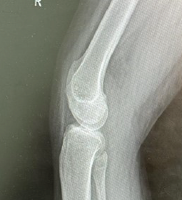

X-ray imaging revealed no foreign body and no joint or bone pathology. Considering the size, location, and benign features of the mass, further imaging was not felt indicated. The patient was diagnosed with a 1 cm × 1 cm fluid filled subcutaneous mass over the anterior aspect of the inferior pole patella. Conservative and operative treatment options to remove the mass were suggested. Considering the amount of sensitivity, the patient was experiencing, the decision to proceed with surgical excision was made.